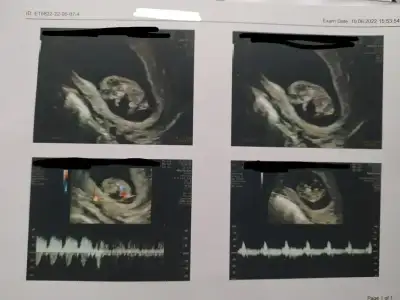

Bu erkek oluyor galiba değil mi ?12+1 çıktı

Kiz olunca üç çizgi oluyormus bunda 2 var sanki

Nuba göre bakılmıyor mu bu haftalarda bilmiyorum kiBu erkek oluyor galiba değil mi ?